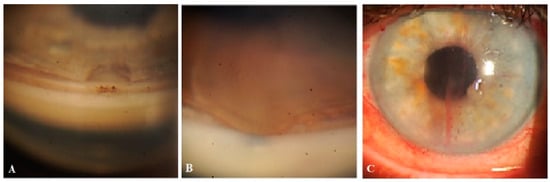

Figure 1. OCT evaluation: (A) OCT scan of the surgery site, showing the collagen implant in the intrascleral reservoir, covered by a superficial scleral flap (SSF) and conjunctiva (CO). No filtration bleb cavity can be observed over the implant or in the nearby area. A conjunctival lymphatic vessel (CLV) can be observed running horizontally over the surgical site. (B) OCT scan of conjunctiva adjacent to the surgical site showing a CLV with valve-like structures (VLSs) in its lumen (white and black arrows with black and white borders). CO = conjunctiva; CLV = conjunctival lymphatic vessel; SSF = superficial scleral flap; VLS = valve-like structure.